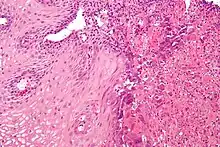

Laboratory tests can be done on biopsies removed from the esophagus and can help determine the cause of the esophagitis. Laboratory tests can help diagnose a fungal, viral, or bacterial infection. Scanning for white blood cells can help diagnose eosinophil esophagitis.

Although it usually assumed that inflammation from acid reflux is caused by the irritant action on the mucosa by hydrochloric acid, one study suggests that the pathogenesis of reflux esophagitis may be cytokine-mediated.[6]

Eosinophilic esophagitis is caused by a high concentration of eosinophils in the esophagus. The presence of eosinophils in the esophagus may be due to an allergen and is often correlated with GERD. The direction of cause and effect between inflammation and acid reflux is poorly established, with recent studies (in 2016) hinting that reflux does not cause inflammation.[6] This esophagitis can be triggered by allergies to food or to inhaled allergens. This type is still poorly understood.

Lymphocytic esophagitis is a rare and poorly understood entity associated with an increased amount of lymphocytes in the lining of the esophagus.[1] It was first described in 2006. Disease associations may include Crohn's disease, gastroesophageal reflux disease and coeliac disease. It causes similar changes on endoscopy as eosinophilic esophagitis including esophageal rings, narrow-lumen esophagus, and linear furrows.